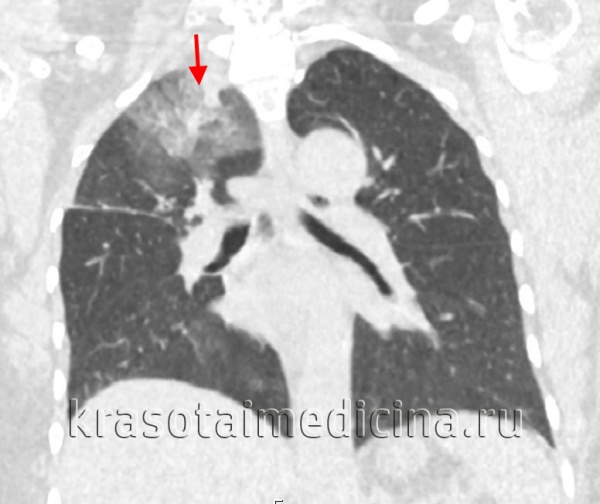

КТ органов грудной клетки. Инфильтрация верхней доли правого легкого у пациента с верифицированным туберкулезом

Дифференцировать инфильтративный туберкулез легких приходится с очаговым туберкулезом, ОРВИ, неспецифической пневмонией, раком легкого, актиномикозом, эхинококкозом и кистами легкого, лимфогранулематозом.